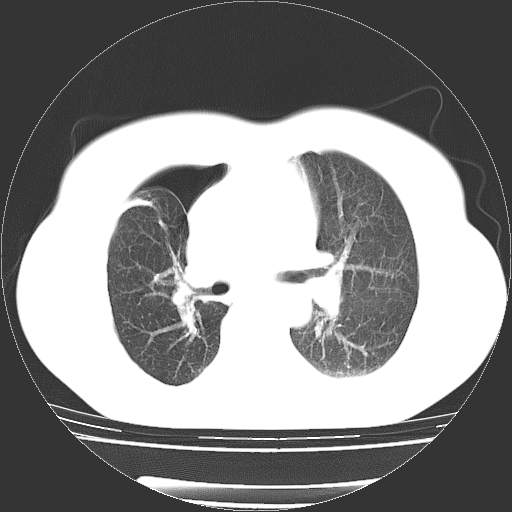

以下是引用zhangzhongshou在2008-3-22 12:52:00的发言:[br]1、右侧液气胸。[br]2、腹水。建议进一步检查。

以下是引用鲁巨ct在2008-3-22 14:10:00的发言:[br]1、右侧液气胸,右中下叶节段性不张。[br]2、腹水,建议上腹部ct检查

以下是引用zjzjr在2008-3-22 17:19:00的发言:[br]1、右侧液气胸,右下叶节段性不张。[br]2、腹水,建议上腹部ct检查